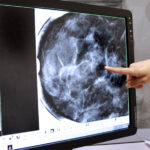

Cada año en el Instituto Mexicano del Seguro Social (IMSS) se realizan un promedio de casi 19 millones de estudios radiológicos en unidades médicas y hospitales en los tres niveles de atención, imágenes que son utilizadas en el diagnóstico oportuno de lesiones o enfermedades e incluso como opción terapéutica intervencionista.

La Dirección de Prestaciones Médicas del Instituto informó que la Radiología consiste en es el uso médico de rayos X para obtener imágenes internas del organismo que lleven a un diagnóstico médico certero de problemas como fracturas óseas o tumores.

Los estudios o procedimientos en los cuáles se usa de forma más frecuentemente son Rayos X simples para las regiones anatómicas del cuerpo, Rayos X simples con equipo portátil, Rayos X especiales o contrastados, estudios de Tomografía Computada y mastografía, así como radiología intervencionista.

El objetivo fundamental de las técnicas radiológicas es prolongar la vida con calidad de los pacientes, disminuir la morbilidad y como apoyo para tratamiento y seguimiento médico de los pacientes que permita restaurar y mantener la salud.